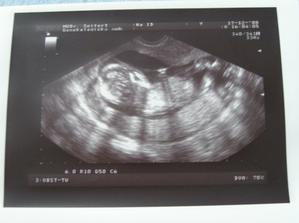

13.1.2009 kontrola dopadla na jedničku, neschopenka trvá a potrvá až do konce. Další kontrola 27.1. a to nás čeká velký UTZ ve 20tt, tak snad se nám ten náš drobeček ukáže. Váhový přírustek zatím stále žádný.//////

27.1. proběhl velký UTZ, který dopadl na jedničku, mimi měří 22 cm a maminka přibrala od minula 1kg, takže už máme pouze -2kg z počáteční váhy, jsem zvědavá, jak rychle to teď poletí...🙂 a hlavně čekáme maminky vytouženou holčičku...🙂 tatínek je taky rád, jen se těšil na chlapečka////////